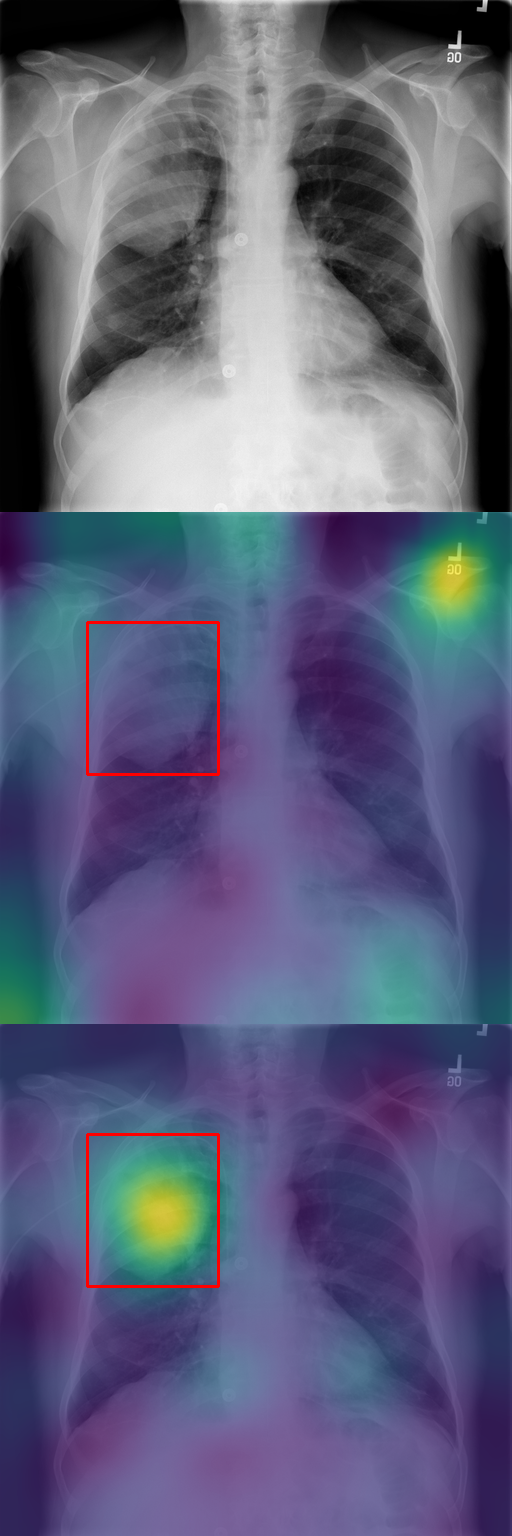

In Section 4.2, we discussed how typicality helps find relevant patches for an input label. In this section, we test this idea on completely different images: X-rays of patients who may suffer from a combination of various thorax diseases. We finetune Stable Diffusion on the ChestX-ray8 dataset [46] containing 108,948 frontal-view X-ray images annotated with 14 single-word disease-name labels. Experts annotated a test set of 879 images with 7 diseases with rectangular regions of interest (ROI) for each disease. For each image, we compute typicality per latent feature, interpolate the resulting typicality to the input dimension, and blur the resulting typicality map for visualization. In Fig. 11, we show the resulting typicality maps together with the ROI annotation before and after finetuning. Finetuning clearly improves the localization. We quantify this effect by computing the area under the precision recall-curve [5] (AUC-PR) associated with the ROIs. As reported in Fig. 11, we see consistent improvement of this measure when finetuning the network (from 3.2% to 9.6%), ranging from +3.5% for Pneumonothorax (from 3% to 6%) to +14.6% for Mass (from 2% to 16.6%), which are respectively the least and most localized diseases. Similar to our other experiments, finetuning uses only image labels without localization supervision.